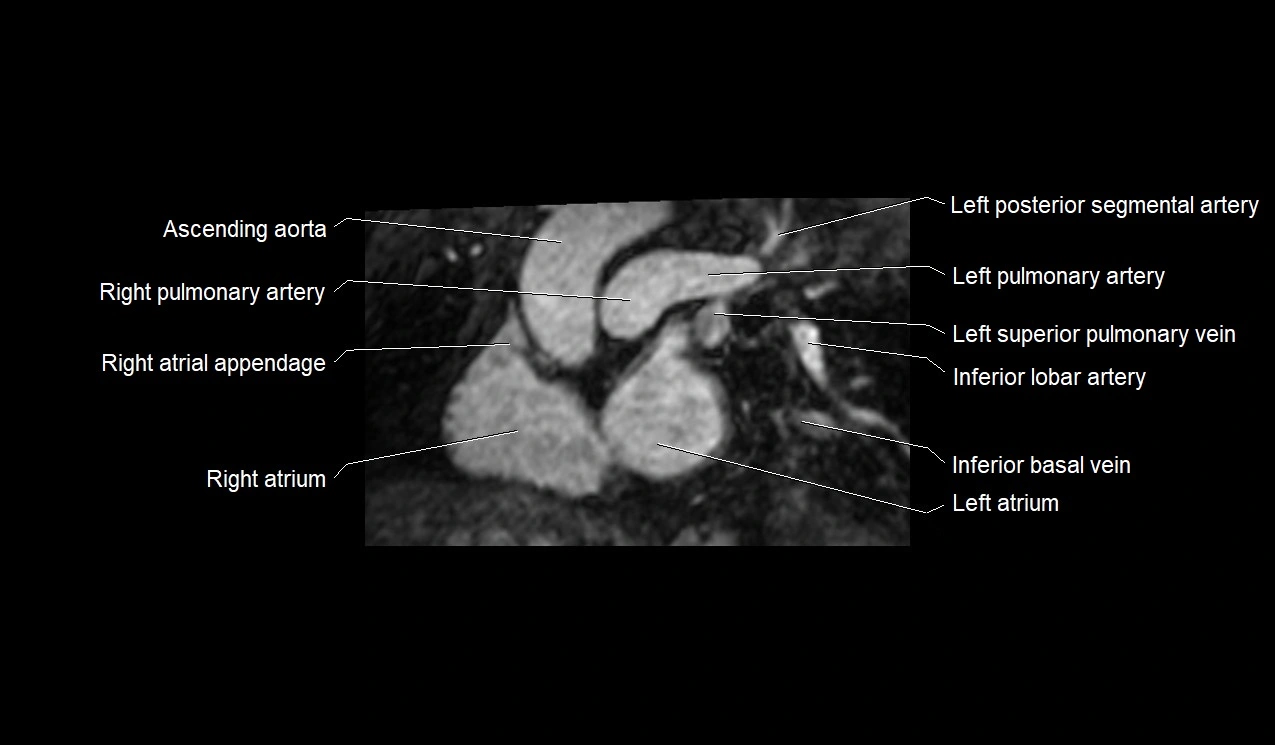

MRI image